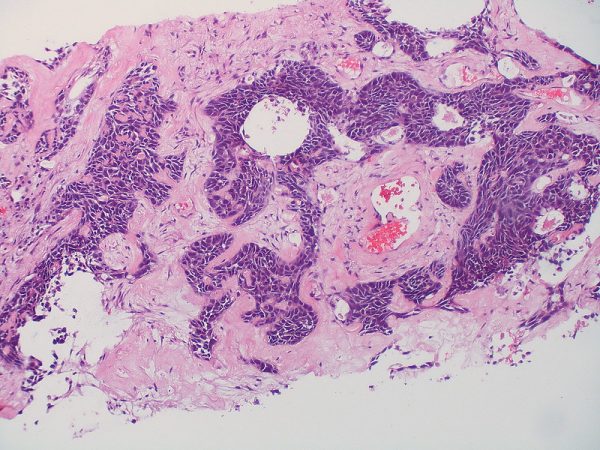

Τα παραπάνω επισήμανε στο in.gr o Παθολόγος-Ογκολόγος Νίκος Α. Κατιρτζόγλου, MDPhD μιλώντας για τον μη μικροκυτταρικό καρκίνο του πνεύμονα, τον τύπο της ασθένειας που αποτελεί το 80-85% των περιστατικών – τα υπόλοιπα περιστατικά αφορούν μικροκυτταρικό τύπο. Ο κάθε ένας από τους δύο τύπους καρκίνου πνεύμονα διαθέτει αρκετούς υποτύπους, ανάλογα με τα γονιδιακά τους χαρακτηριστικά που αποτελούν και τη μοριακή «υπογραφή» του όγκου.

Έτσι, στη κλασική χημειοθεραπεία (που και αυτή πλέον διαφέρει – ανάλογα με το εάν ο καρκίνος του πνεύμονα είναι αδενικού ή πλακώδους τύπου) έχουν προστεθεί οι στοχευτικοί παράγοντες (Στοχευμένη Θεραπεία), η αντι-αγγειογενετική θεραπεία και η ανοσοθεραπεία. Παραδοσιακά, ο πρώιμος καρκίνος πνεύμονα αντιμετωπίζεται μεχειρουργική θεραπεία, ενώ σε αρκετές περιπτώσεις εφαρμόζεται και η ακτινοθεραπεία, η οποία και αυτή έχει συγκεκριμένες ενδείξεις.